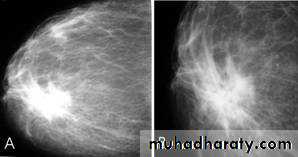

Breast density & who can U detect a mass lesionYour mammogram report must take in consideration & assessment the breast density. Breast density is based on how fibrous and glandular tissue tissues are distributed in your breast, vs. how much of your breast is made up fatty tissue.

Dense breasts are not abnormal, but they are linked to a higher risk of breast cancer. We know that dense breast tissue can make it harder to find cancers on a mammogram. Still experts do not agree what other tests, if any, should be done in addition to mammograms in women with dense breasts who aren’t in a high-risk group (based on gene mutations, breast cancer in the family, or other factors

Before u asses the mass look at their margin